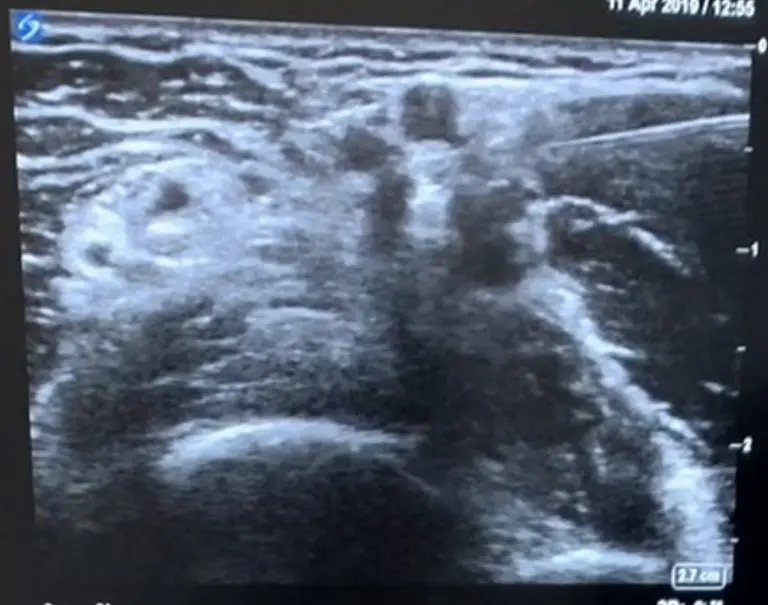

下記は40代女性右手を酷使する仕事で右手の前腕の痺れと痛みで来院、他院では頸椎症性神経根症として牽引などの治療されていましたが、身体所見からそちらは一度除外し前腕にエコーを当てたところ下記の所見がありました。

エコーでは両方の神経の周りがもやもや白くなっているのがわかりますよね

病名は円回内筋症候群 絞扼疾患の一つです

剥離前

正中神経を剥離しました。剥離前は周り全体が白かったですが、剥離後は神経が明確に描出されていることがわかります。